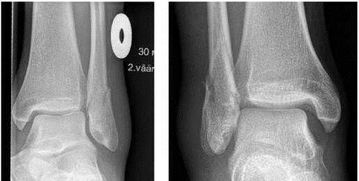

你的骨折情況看你說(shuō)不像很?chē)?yán)重,你自己看的還是醫(yī)生看的?如果確定還有裂痕,那你現(xiàn)在的情況挺尷尬的。

一般來(lái)說(shuō)固定三周了,骨折線應(yīng)該已經(jīng)模糊了。但你這種只是有點(diǎn)遲緩愈合,也是正??赡艿那闆r。

首先,腳踝骨折了一定要注意到骨外科拍片做個(gè)詳細(xì)的檢查,在局部的地方進(jìn)行復(fù)位固定,在此期間切記不要隨意亂動(dòng),讓骨折位置能夠快速?gòu)?fù)原,避免移位那就麻煩。